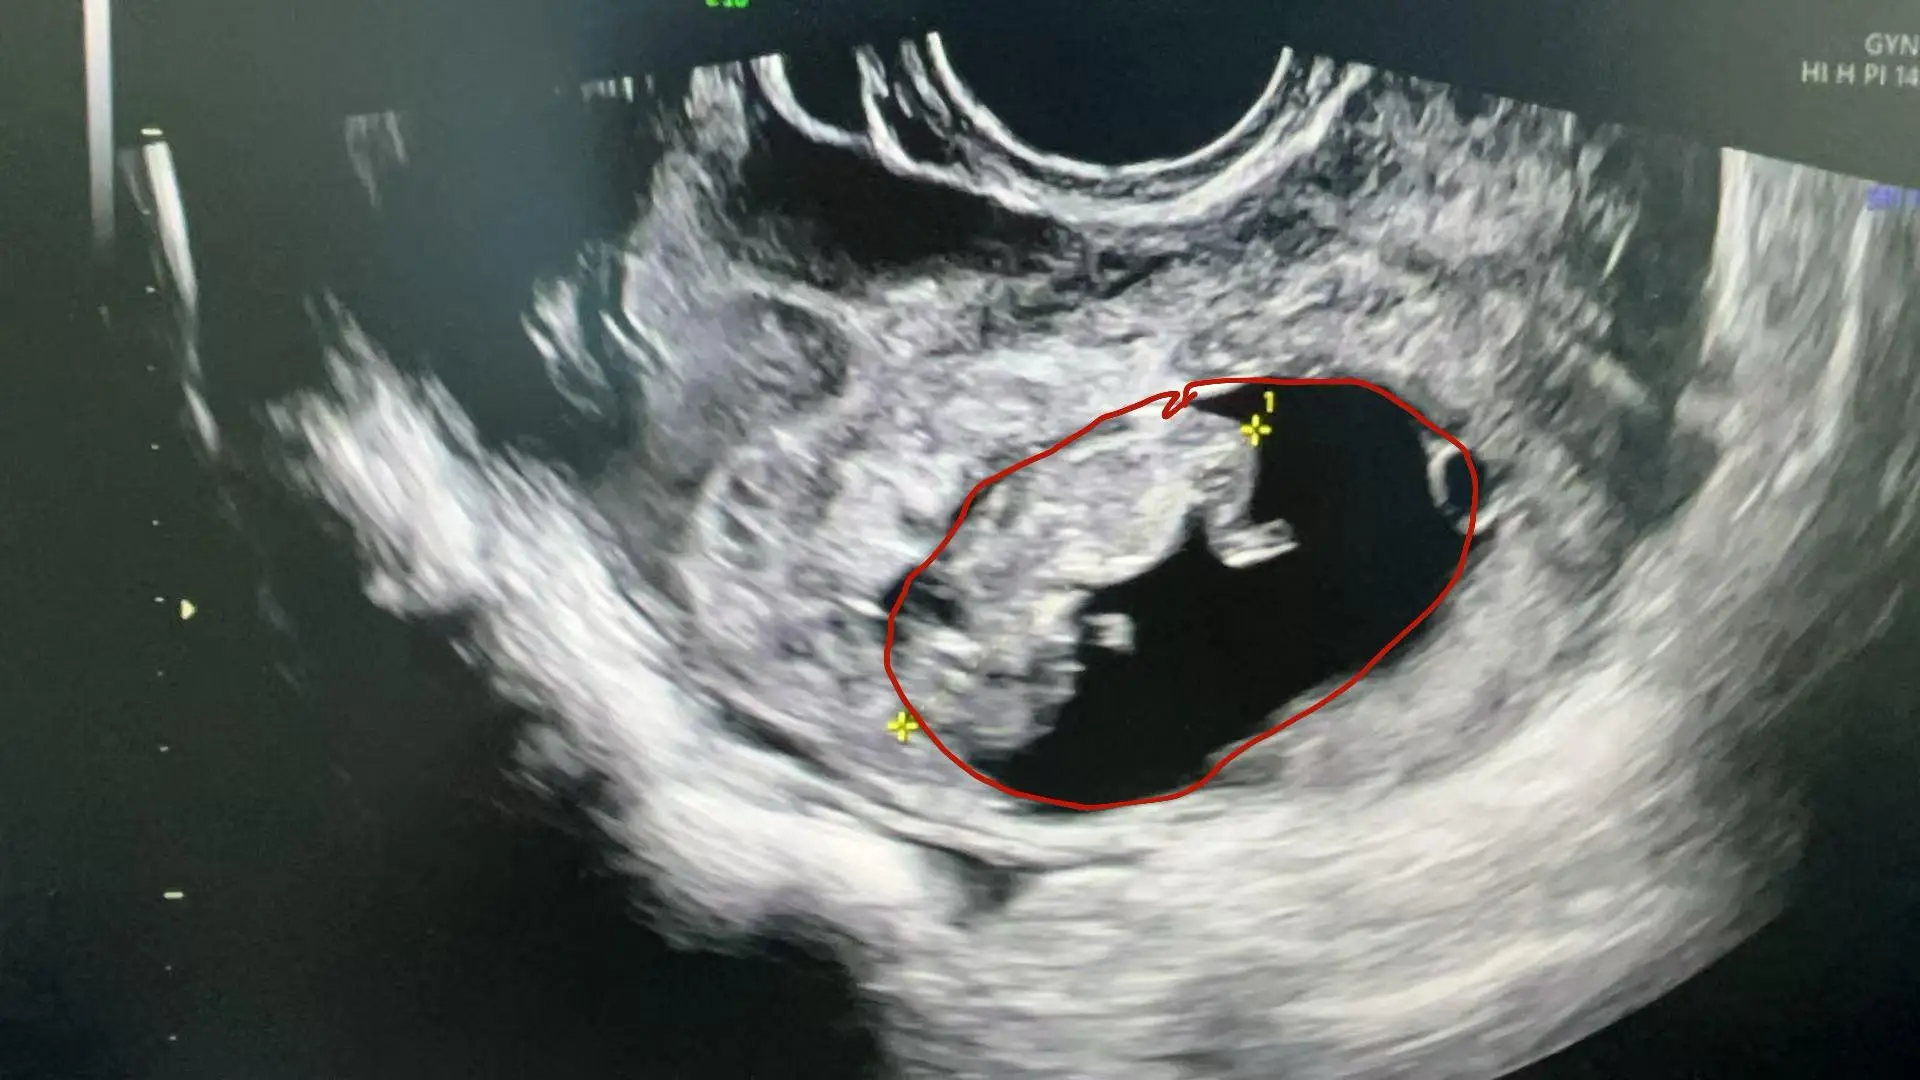

Kết quả xét nghiệm nước tiểu xác nhận cô đang mang thai. Siêu âm khẩn cấp cho thấy có rất nhiều dịch máu trong ổ bụng và vùng chậu, trong khi tử cung lại không chứa túi thai. Thay vào đó, một khối bất thường nằm ở phía trên bên trái tử cung, có chứa phôi thai và dấu hiệu tim thai - dấu hiệu đặc trưng của một ca thai ổ bụng, tình trạng cực kỳ hiếm gặp và nguy hiểm.

Ảnh chụp bào thai trong ổ bụng của cô Cốc.